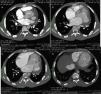

A 24-year-old black man presented to the emergency department of our hospital with fatigue and dyspnea at rest of two weeks duration. The transthoracic echocardiogram (Figure 1) revealed aneurysm of the right sinus of Valsalva (Figure 1A) dissecting into the interventricular septum (arrow) (Figure 1B), dilated left ventricle with moderately to severely impaired systolic function, and echocardiographic criteria for left ventricular non-compaction (Figure 1C and D). A submitral aneurysm and a dilated left atrium were also observed (Figure 1C). Doppler echocardiography showed mild mitral and aortic regurgitation. Multislice computed tomography with contrast (Figure 2) revealed an aneurysm of the right sinus of Valsalva (Figure 2A) dissecting into the interventricular septum (arrow) (Figure 2B), as well as a submitral aneurysm (Figure 2C) and non-compaction of the left ventricle (Figure 2D), confirming the echocardiographic findings. The patient was admitted to the cardiac intensive care unit of our hospital and treated with diuretics, angiotensin-converting enzyme inhibitors and digitalis, with dramatic improvement in symptoms. He was proposed for surgery but refused and was discharged in New York Heart Association class I. The patient died one year after the first admission.